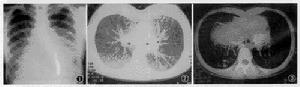

1.肺大泡體積大,占據一側胸腔的1/3~1/2以上,臨床上有症狀,而肺部無其他病變

的患者,手術切除肺大泡可以使受壓肺組織復張,呼吸面積增加,肺內分流消失,動脈血氧分壓提高,氣道阻力減低,通氣量增加,患者胸悶、氣短等呼吸困難症狀可以改善(圖2)。